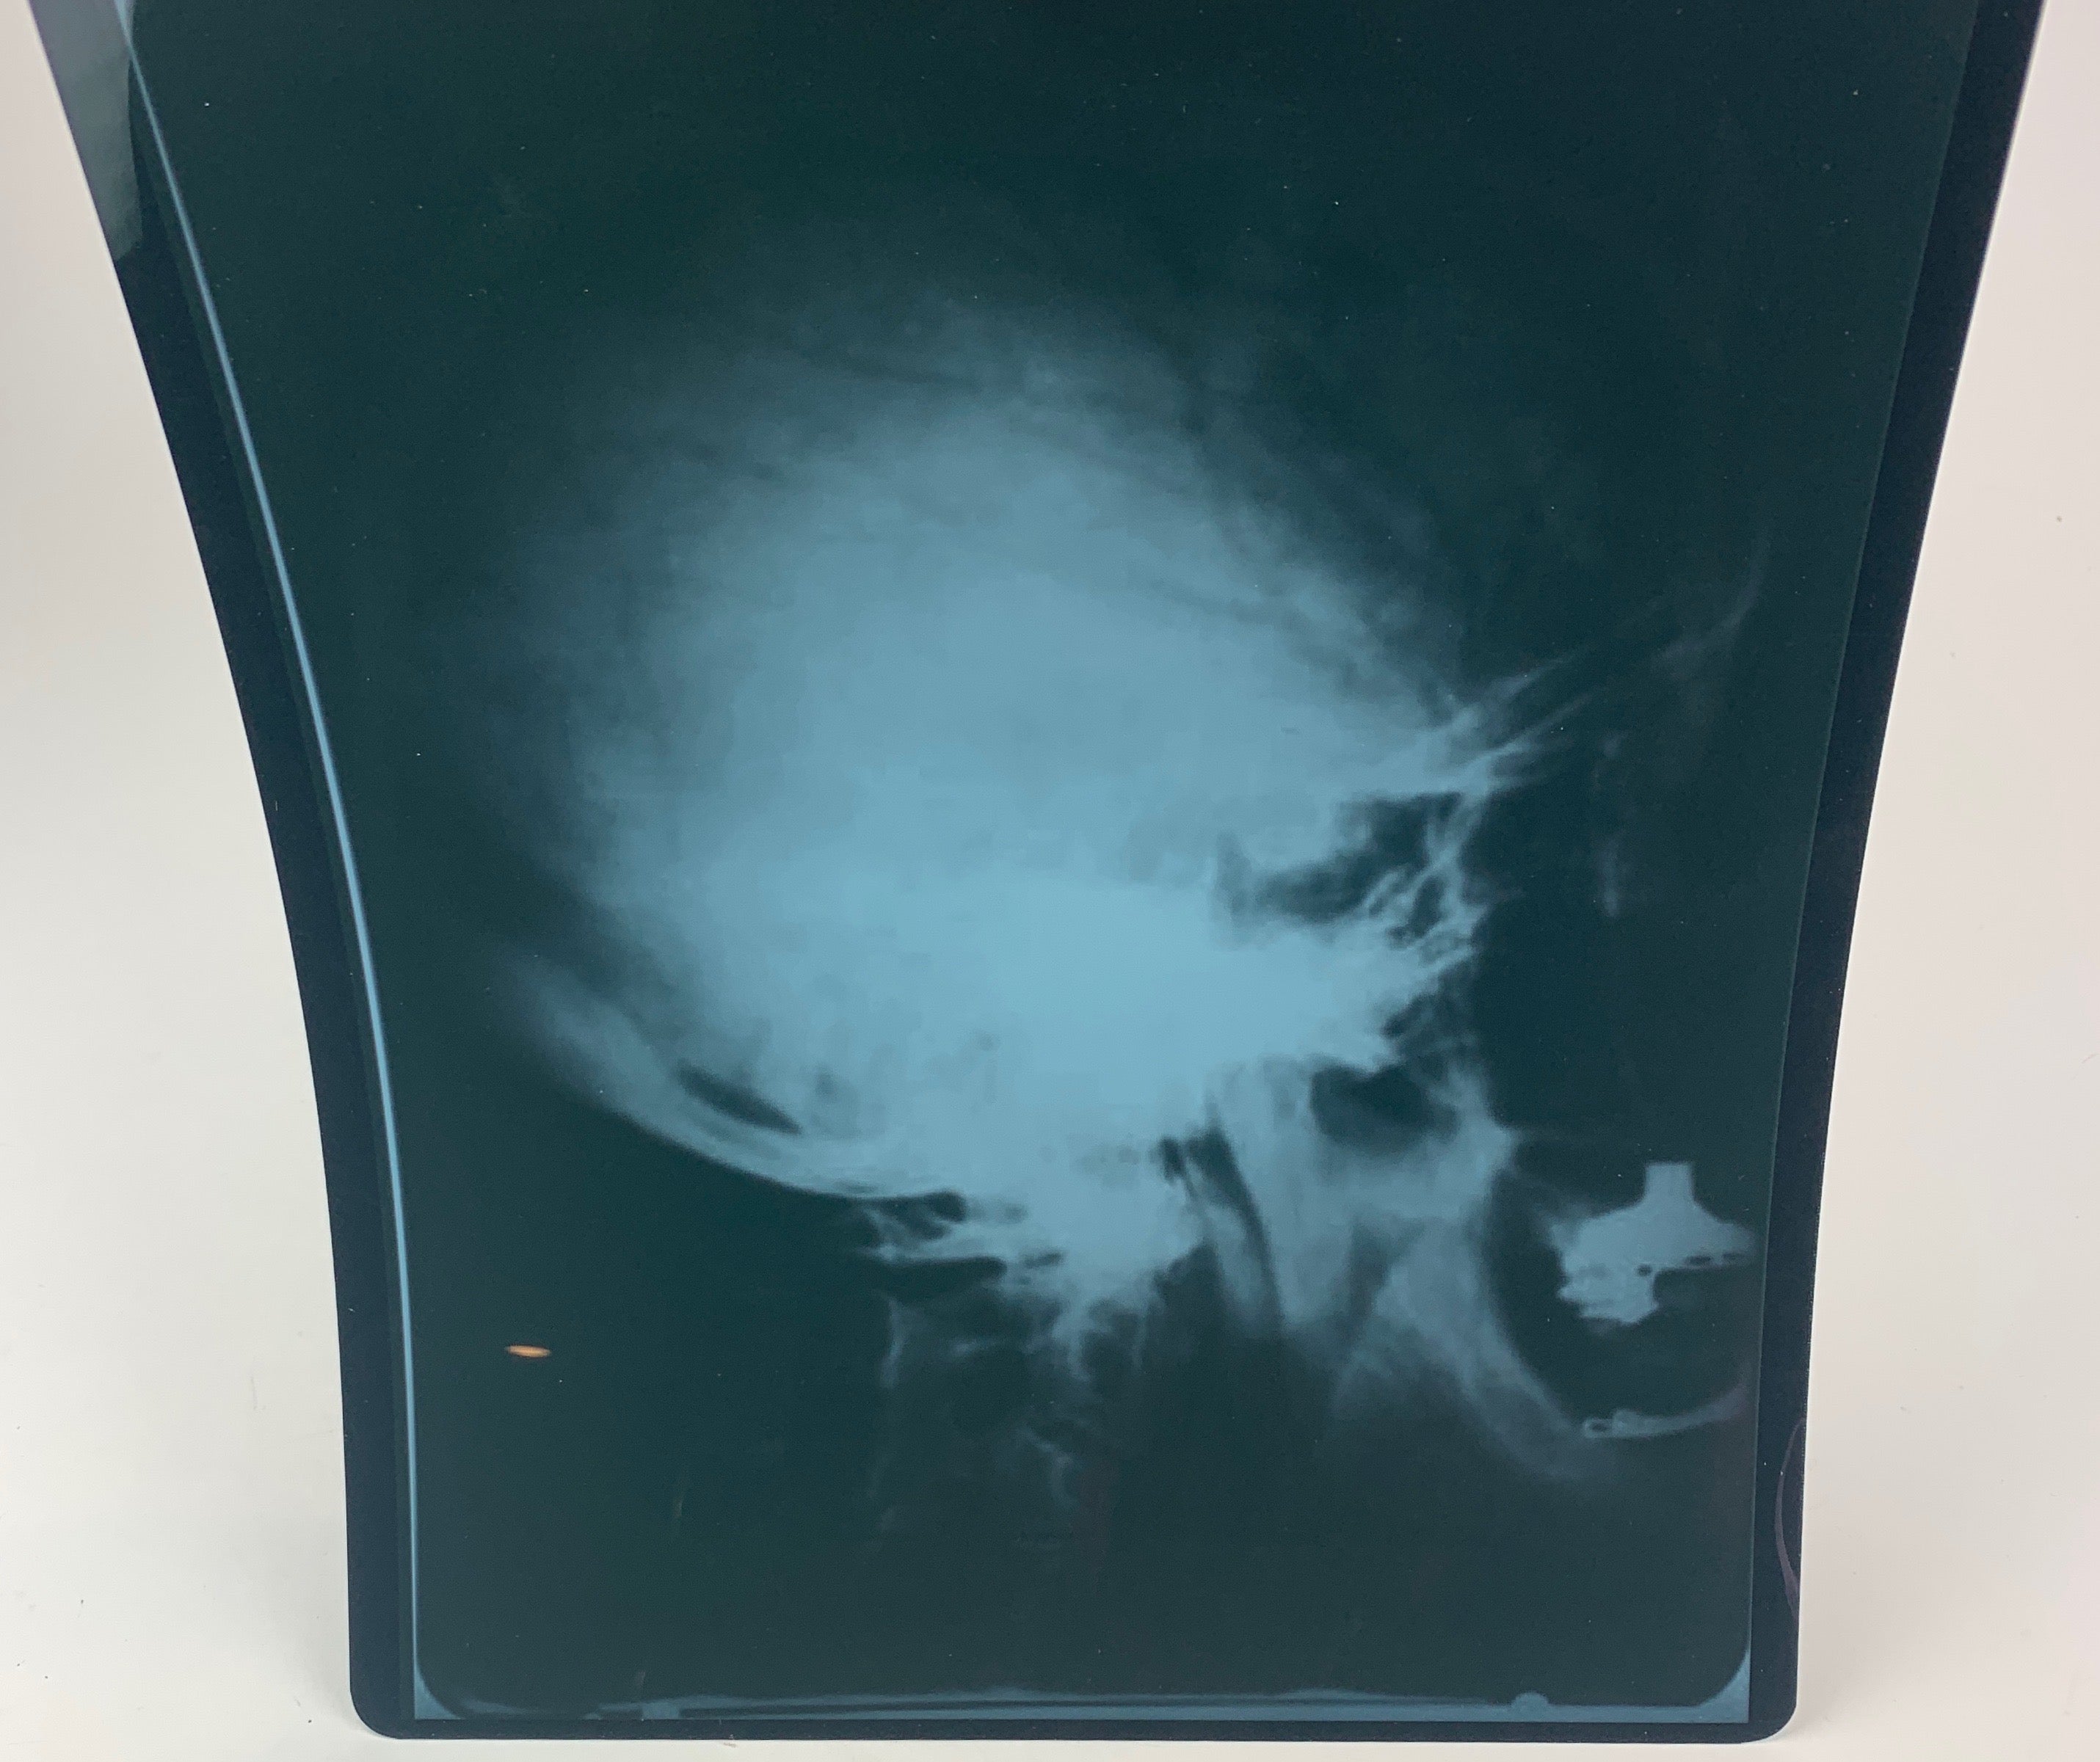

[Einstein, Albert. (1879 - 1955)]. Photograph of Einstein's Brain Waves!. Medical side view X-ray of Albert Einstein's skull, taken in 1945 by Dr. Gustav Bucky. In very fine condition. Printed on standard X-ray photograph stock, 10 x 12 inches (25.2 x 30.2 cm). We have been unable to positively identify when this print was made, but it is not one that either Bucky or Einstein owned and certainly dates from well after the original imaging. Another example of the present X-ray together with a peripheral view (both also later printings), sold on December 2010 at auction for $38,750.00.

Gustav Bucky was a forerunner in radiograph technology and inventor of the Bucky Screen, which allowed for sharper radiograph images. Bucky and Einstein were co-inventors of the Automatic Electric Eye Camera. In 1933, like Einstein, Bucky, who in 1913 had developed a two-plate system that made x-rays a practical medical application, immigrated to the United States where the two met in 1933 while Bucky was treating Einstein’s wife, Elsa. They became close friends and Einstein helped Bucky patent some of his radiological inventions. Additionally, in 1935, they patented a camera that could automatically adjust for exposure using a photoelectric sensor; the camera was never built, however, and with the 1938 production of the automatic Super Six-20, Kodak was credited with creating the first automatic exposure camera. The two remained close friends, and Bucky was at Einstein’s bedside at the time of his death.